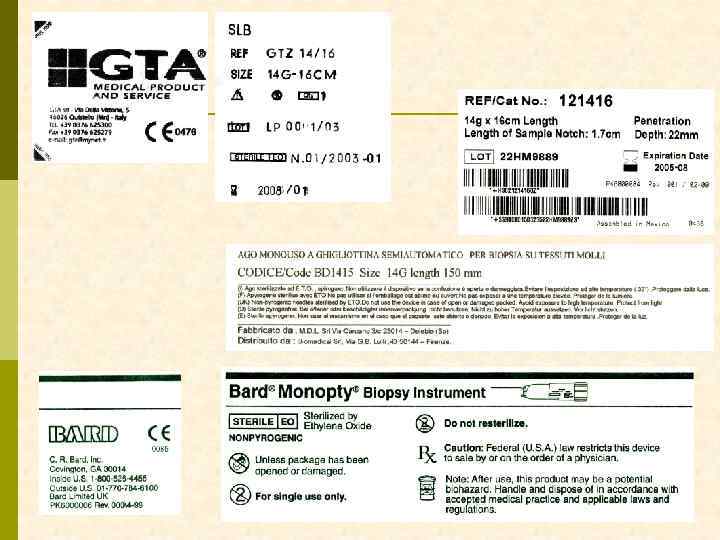

ЧТО НУЖНО ДЛЯ ВЫПОЛНЕНИЯ ДИАГНОСТИЧЕСКОЙ НЕФРОБИОПСИИ? Биопсионная игла Vim-Silverman’a игла Tru-Cut игла с пружиной Аппарат ультразвуковой диагностики (с ультразвуковой поддержкой нефробиопсия выполняется быстрее, но частоту осложнений она не уменьшает) А также: шприц 10– 20 мл, игла для п/к введения анестетик (новокаин 0, 5% 20– 40 мл) игла инъекционная 100– 120 мм скальпель предметное стекло консерванты для биоптата (N 3 !!)

БИОПСИОННАЯ ИГЛА Tru-Cut Baxter

АВТОМАТИЧЕСКАЯ (С ПРУЖИНОЙ) БИОПСИОННАЯ ИГЛА Meditech

АВТОМАТИЧЕСКАЯ (С ПРУЖИНОЙ) БИОПСИОННАЯ ИГЛА Monopty

Monopty